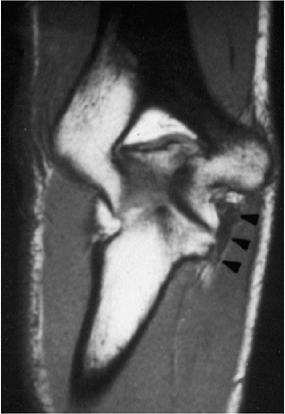

![]() |

Figure 14-6. Magnetic resonance imaging (MRI) showing edema and fiber injury in the ulnar collateral ligament (arrowheads).